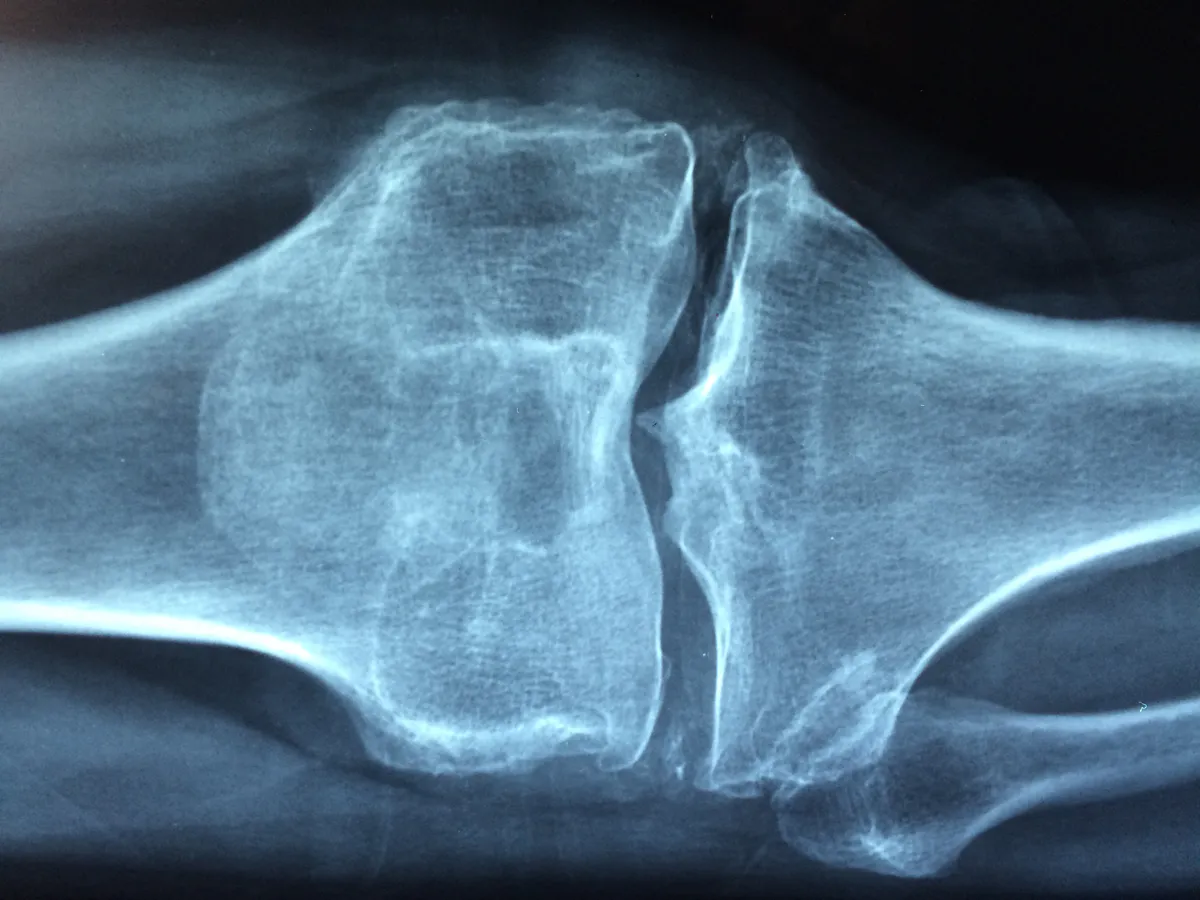

С одной стороны, она дает суставам необычную подвижность, делает их «живыми». С другой — меняет естественные векторы движения, и с раннего возраста это создает неправильные точки приложения сил. ДСТ напрямую влияет на будущую износостойкость суставов и чревато различными последствиями. Например, со стороны стопы это часто ведет к плоскостопию и его осложнениям. Для коленных суставов проблема может быть в основном эстетической — избыточном выпячивании коленей назад. В тазобедренных суставах у взрослых изменения обычно малозначимы, но в младенчестве, до начала ходьбы, повышенная растяжимость может привести к вывиху. Со стороны спины ДСТ нередко приводит к формированию сколиоза различной степени. В плечевых суставах гипермобильность проявляется склонностью к подвывихам, хроническим щелчкам и болевым синдромам. Локтевые и лучезапястные суставы, а также пальцы кистей чаще демонстрируют лишь эстетический эффект избыточного сгибания-разгибания и легкую нестабильность.